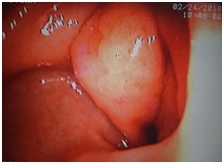

Эзофагогастродуоденоскопия

Выходной отдел желудка выраженно деформирован за счет опухолевидного образования до 4 см, осмотр несколько затруднен вследствие локализации и деформации просвета, определяется язвенный дефект в центре до 10 мм с прикрытым фибрином дном.

Выполнена биопсия для гистологического исследования; слизистая при биопсии ригидная, хрящевидной плотности, фрагментируется, выраженно кровоточит.

Заключение. Опухолевидное образование антрального отдела желудка с переходом на привратник с деформацией и незначительным сужением просвета, биопсия.